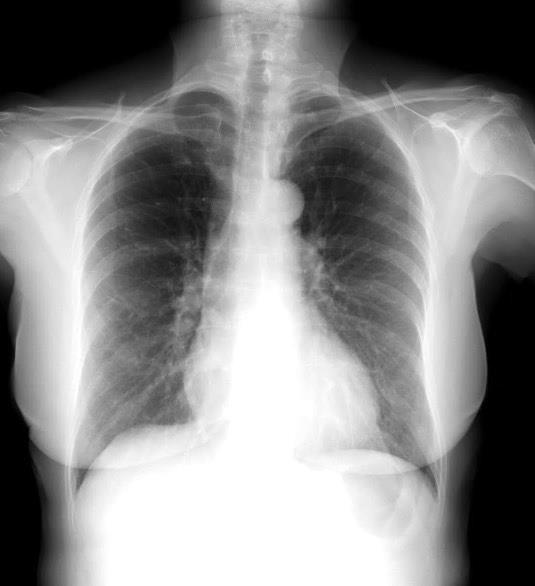

Normal